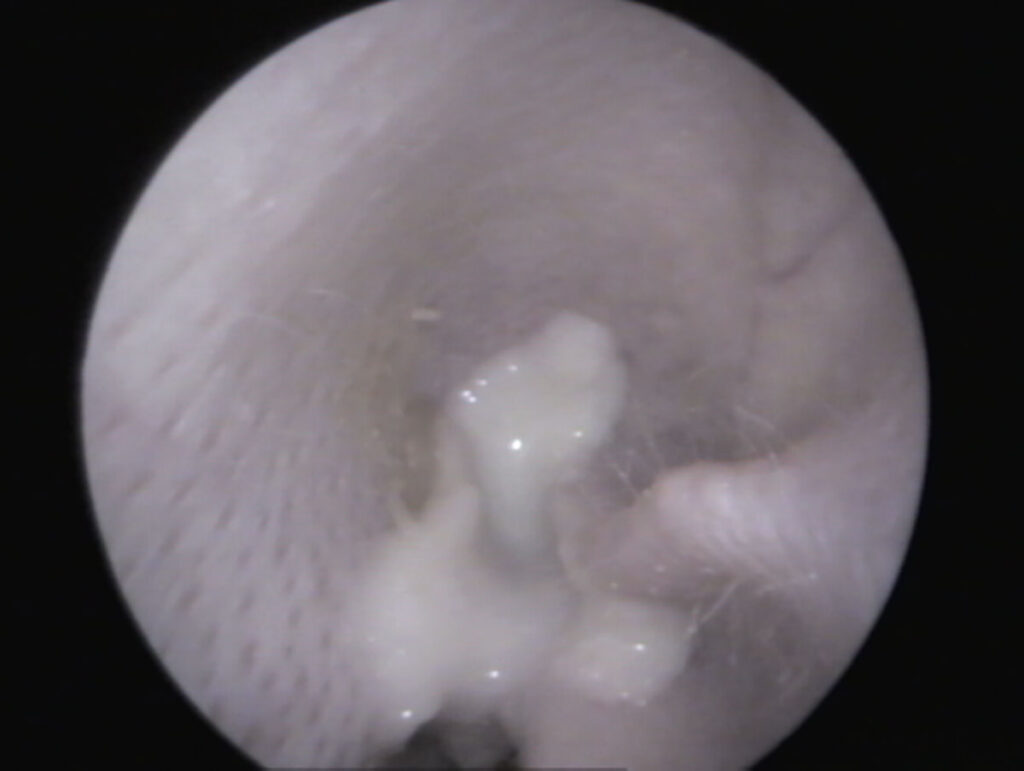

In un orecchio sano, tirando delicatamente il padiglione auricolare verso l’alto (Fig. 1), si riesce solitamente a vedere fino al timpano (Fig. 3). Se è presente materiale nel condotto uditivo, è importante distinguere se si tratta “solo” di cerume accumulato (bianco in profondità, giallastro verso l’orifizio) e il condotto uditivo è altrimenti normale, oppure se sono presenti segni di infiammazione (arrossamento, gonfiore, lesioni, liquefazione del secreto) (Fig. 4) e possibili cause primarie come corpi estranei e/o ectoparassiti.

Fig. 4: Vista dell’orecchio esterno pieno di pus di un coniglio – l’orecchio esterno senza alterazioni suggerisce che il pus provenga dall’orecchio medio

Fonte: J. Hein